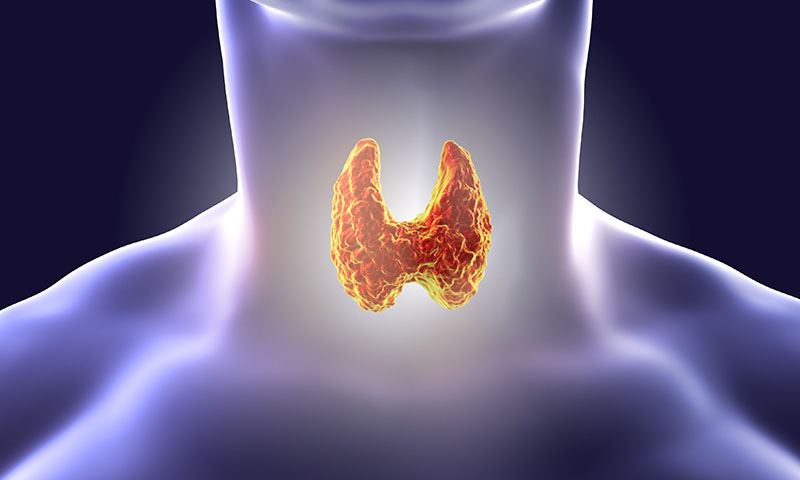

به گفته محققان، غده تیروئید، غده کوچکی که هورمونهای حیاتی تولید میکند میتواند تأثیر زیادی بر سیستم قلبی عروقی داشته باشد.

غده تیروئید که در پایه گردن قرار دارد، هورمونهایی را ترشح میکند که متابولیسم را تنظیم کرده و بر هر اندام از جمله قلب تأثیر میگذارد. هنگامی که بدن بیش از حد هورمون تیروئید تولید میکند، نتیجه پرکاری تیروئید است که میتواند باعث ضربان قلب نامنظم شود و منجر به لخته شدن خون، سکته مغزی و نارسایی قلبی و همچنین پوکی استخوان و سایر مشکلات شود.